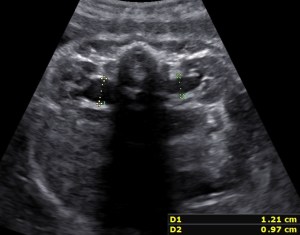

- Maximum AP RPD (Antero-Posterior Renal Pelvic Diameter) in the transverse plane with spine at 12 (or 6) o’clock.

Unilateral hydronephrosis in a case of megaureter.